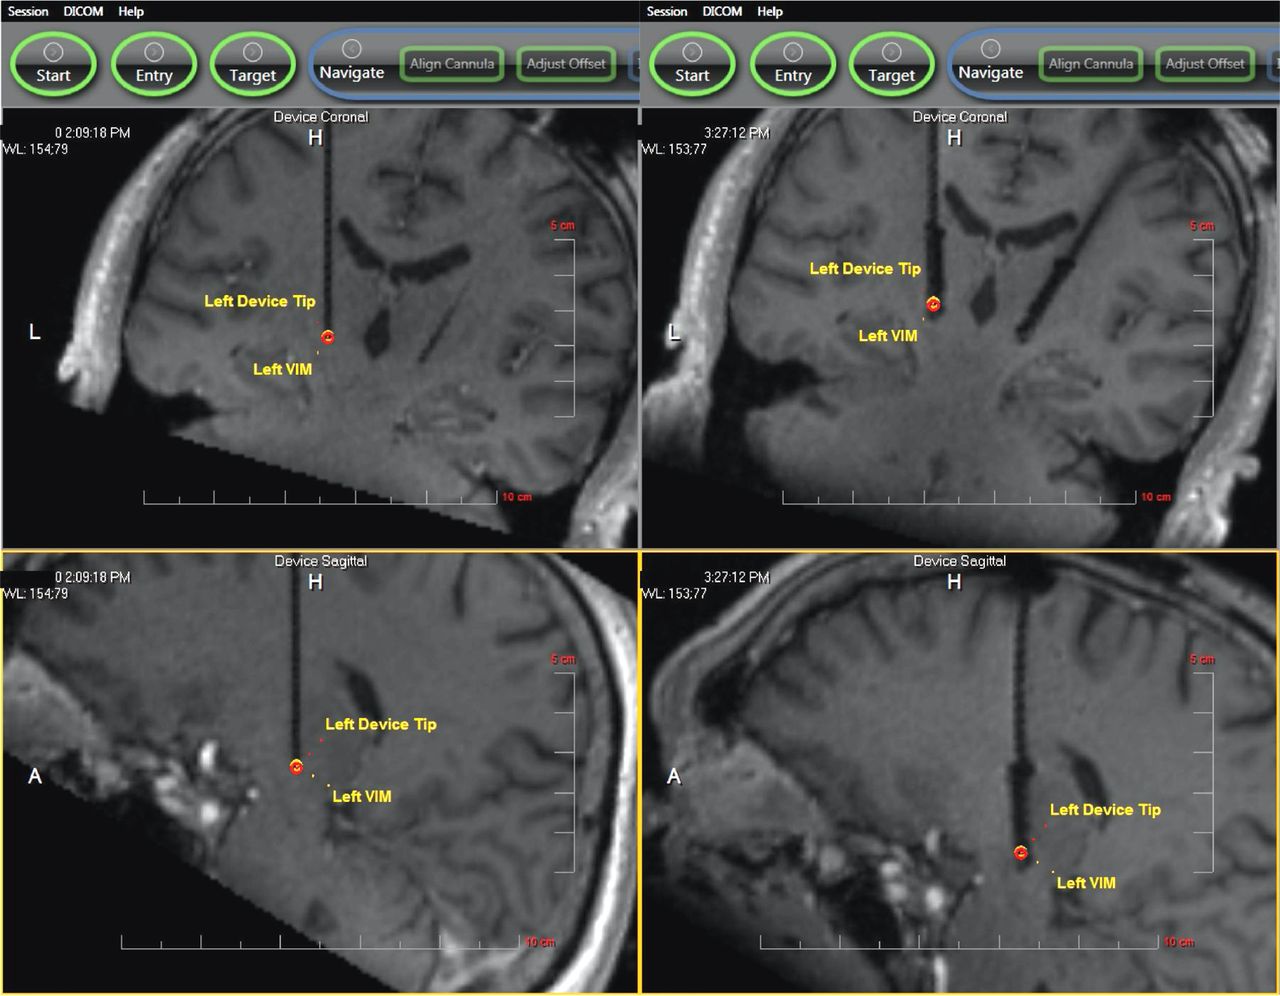

The procedure for iMRI-DBS placement has been described in detail elsewhere.8 In brief, after the induction of general anesthesia, the patient’s head is fixed to the MRI gantry with a custom 4-pin head holder (MRI Interventions). After sterile preparation and draping, the skull entry site is marked through the skin, the scalp is opened, and a skull-mounted miniframe (SmartFrame, MRI Interventions) is rigidly affixed using bone screws. MR imaging scans are obtained according to manufacturer specifications, the target is selected by using intraoperative images, and the miniframe is iteratively adjusted until the cannula is aimed at target with less than 1-mm projected radial error. A ceramic stylet and peel-away sheath are then placed to target, and the actual error is measured. If stylet placement is acceptable (as determined by the surgeon, with 1.5-mm radial error being the usual cutoff), the stylet is replaced by the DBS electrode, and the peel-away sheath is removed. Postplacement images may be performed immediately after electrode placement, with the proximal ends of the electrodes extended within the bore of the scanner (“externalized”), after the electrodes have been secured with silicone boots and coiled under the closed scalp incision (“internalized”), or both. Examples of iMRI are shown in Fig 1.

Sample iMRI before and after DBS placement. The left side of the figure shows intraoperative 3D T1 FLASH images of ceramic stylet placement in the left Vim (upper image, coronal; lower image, sagittal). The right side of the figure shows bilateral DBS electrode placement in the same patient. See “Surgical Procedure” in the Methods section for details.